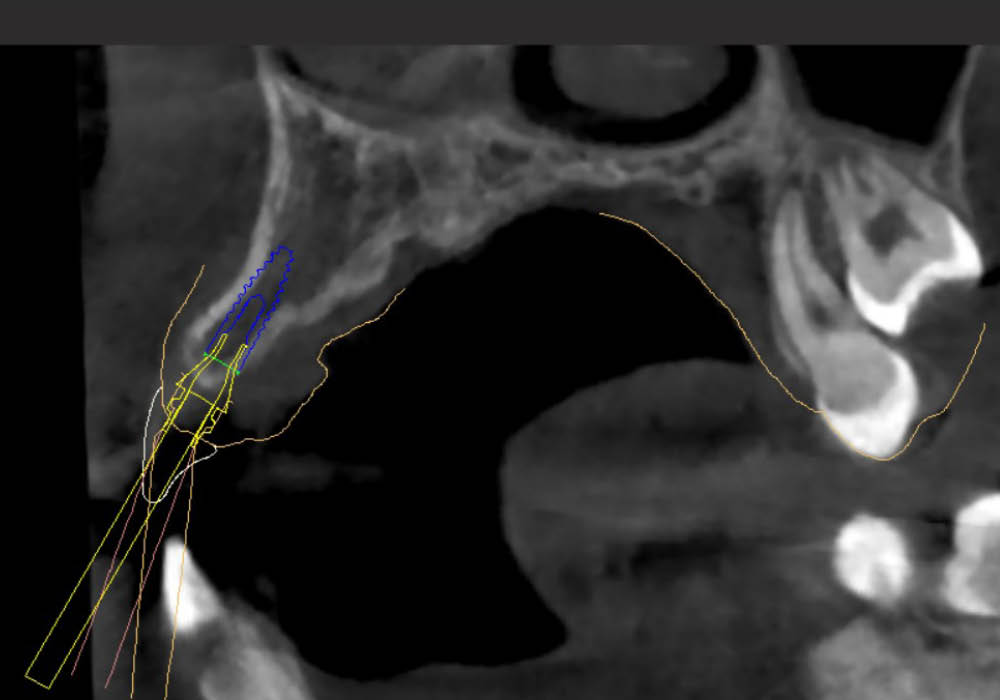

La segmentazione dei dati CBCT è stata effettuata partendo da un file DICOM.

L’utilizzo dell’intelligenza artificiale ha permesso di automatizzare la separazione e la ricostruzione tridimensionale delle strutture anatomiche, facilitando l’elaborazione e garantendo maggiore precisione nella valutazione iniziale.

La pianificazione chirurgica ha previsto un’analisi tridimensionale dettagliata del sito implantare, valutato sia da angolazioni multiple sia in visione frontale diretta.

L’obiettivo era quello di definire con precisione posizione, profondità e inclinazione dell’impianto, tenendo conto della vicinanza delle radici adiacenti e della necessità di preservare un adeguato spessore vestibolare.

Questa fase ha permesso di anticipare eventuali criticità e assicurare l’inserzione corretta all’interno dei limiti anatomici disponibili.